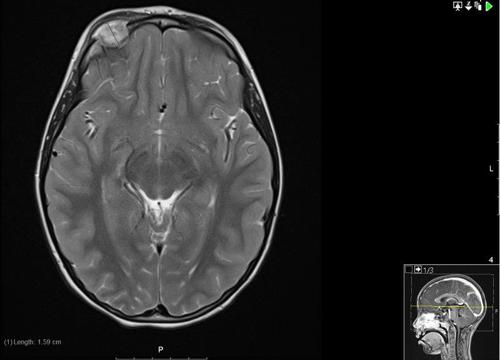

An MRI scan of the orbit, along with a whole-body MRI STIR (to screen for other lytic lesions) were conducted. The MRI demonstrated the soft tissue mass mushrooming through a bony defect with peripheral enhancement, and associated pachymeningeal and leptomeningeal enhancement where the mass bulged against the right frontal lobe (Fig 4). The whole-body STIR showed multiple bilateral abnormalities in the tarsal bones and also the cuboids, which were likely to be bony abnormalities reflecting the patient’s interest in gymnastics.

Fig 4.